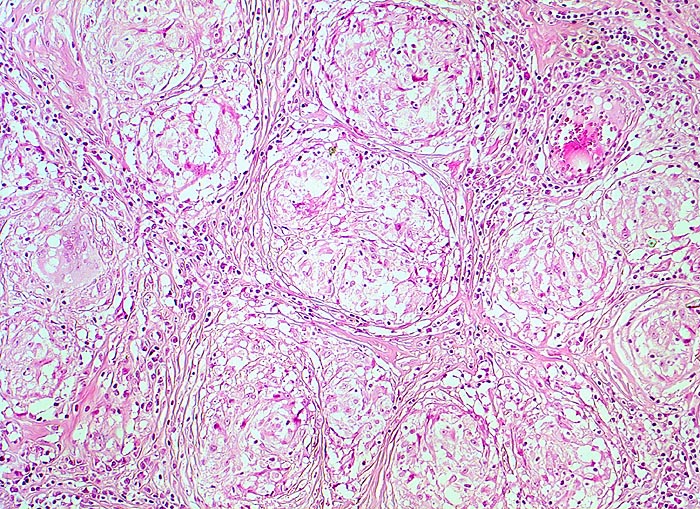

Lymphknotensarkoidose (Morbus Boeck) Granulome mit Fibrose

Lymphknoten, inguinal

Späteres Stadium einer Sarkoidose. Für Sarkoidose typische konzentrische Fibrose in der Peripherie der Granulome. Das Parenchym des Lymphknotens ist verdrängt. Die Granulome stehen Rücken an Rücken und konfluieren nicht.

Bihiläre Lymphadenopathie bei Sarkoidose. Plötzlicher Herztod.

100